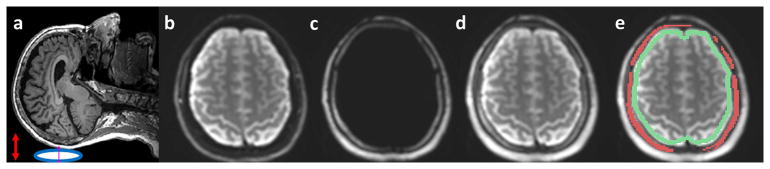

Figure 2.

(a) Brain MRE soft pillow driver positioned beneath the head (blue oval) induces vibrations in anterior-posterior (AP) direction (red arrow). (b–d) Illustration of dual-saturation imaging of a healthy volunteer in a representative slice. (b) MRE magnitude brain image acquired with the water-selective spatial-spectral (SPSP) excitation. (c) MRE magnitude image of scalp-skull acquired with the fat-selective SPSP excitation. (d) MRE magnitude image generated by combining (a) and (b). The recombined image demonstrates excellent depiction of both the skull and brain. (e) Illustration of the skull (red) and brain surface (green) ROIs for motion analysis.

An example of a combined skull-plus-brain MRE image is shown in Figure 2, including brain tissue signal-only (Fig. 2b), skull signal-only (Fig. 2c), and the combined skull-plus-brain images (Fig. 2d) from a volunteer. Note that the skull signal is barely visible in Figure 2b while it is clearly depicted in Figure 2c. The recombined image with a clear depiction of the skull and brain demonstrates the feasibility of this dual-saturation imaging approach. The overall empirical SNR of the skull increased from 4.3 ± 2.4 (with fat-saturation) to 8.9 ± 0.9 (with water-saturation) averaged over 6 volunteers.